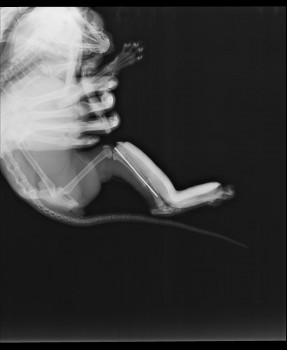

Вкратце: операцию провели, от наркоза кошка отходила очень долго и громко. Наверное в это время и сместила немного кость. Вот снимки через два дня после операции.